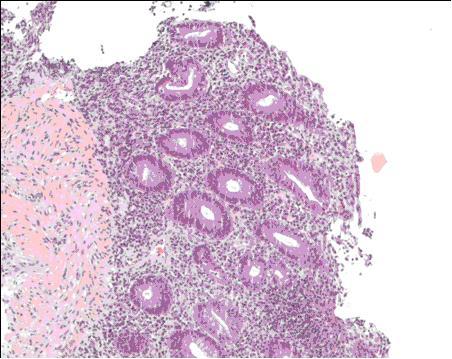

We report a provocative case of UC with profound rheumatologic involvement directly preceded by Clostridium difficile infection and accompanying fever, vomiting, bloody diarrhea, and arthritis. Colonic biopsy revealed a histopathology suggestive of UC. Antibiotic treatment eliminated detectable levels of enteric pathogens but did not abate symptoms. Resolution of symptoms was procurable with oral prednisone, but tapering of corticosteroids was only achievable in combination therapy with vancomycin and metronidazole.

我们报告了一例具有严重风湿性病变的UC激发病例,该病例在艰难梭菌感染后直接出现,并伴有发热、呕吐、血性腹泻和关节炎。结肠活检显示组织病理学提示为UC。抗生素治疗消除了可检测到的肠道病原体水平,但并未减轻症状。口服泼尼松可使症状缓解,但只有在与万古霉素和甲硝唑联合治疗时才能逐渐减少皮质类固醇的用量。